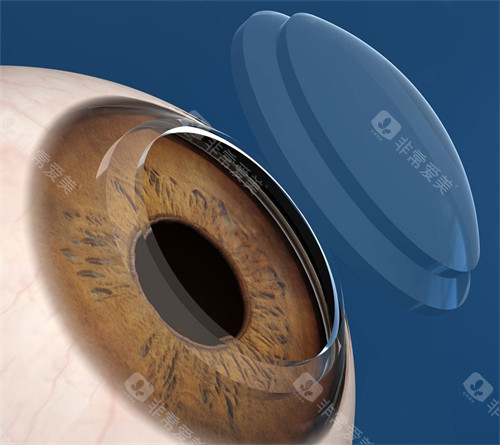

角膜内皮移植:3万元起/单眼

黑科技:3mm微切口植入,无需缝合,术后次日可视物,适合大泡性角膜病变

人工角膜移植:

米赫人工角膜(俄罗斯进口):3.5万元起,长期免更换

Boston Ⅱ型(美国FDA认证):4.5万元起,透氧率提升60%

EndoArt生物角膜(瑞士仿生内皮):5万元起,融合速度加快